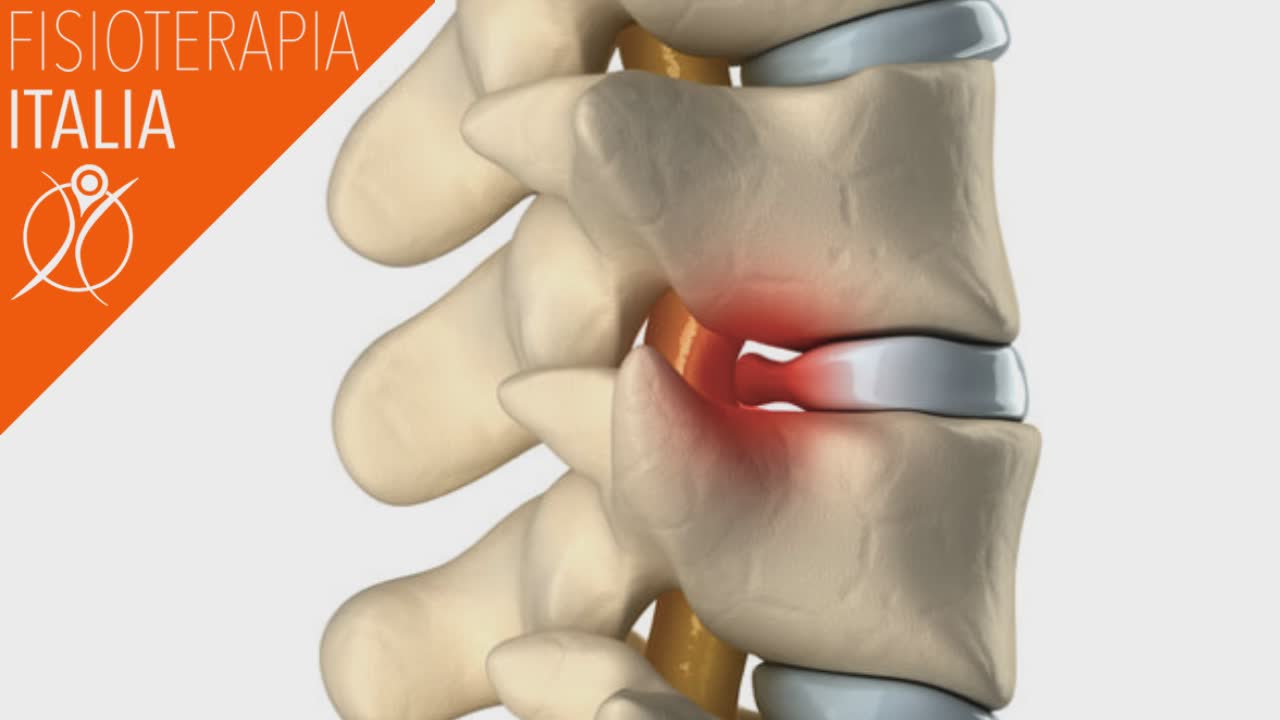

La sciatica è comunemente causata da un certo tipo di compressione di un nervo spinale nella parte bassa della schiena. Il termine medico per la sciatica è dolore radicolare lombare, ciò indica che il sintomo ha origine nella radice nervosa. Le radici nervose, a volte chiamate nervi radicolari, si trovano dove i nervi si dipartono dalla colonna vertebrale.

Queste radici escono dai lati sinistro e destro della colonna attraverso gli spazi tra le vertebre. I sintomi specifici saranno diversi a seconda di quale sia il nervo spinale interessato e di quanto sia compresso. Ad esempio la compressione del nervo crurale da una tipica sintomatologia sulla parte anteriore della coscia a differenza dello sciatico che da sintomi nella parte posteriore. Una diversa varietà di condizioni lombari può portare alla sciatica. Il nervo sciatico può andare in sofferenza principalmente per:

Più comunemente, oltre a un'ernia del disco lombare, che è la causa principale di gravi lombosciatalgie con sintomi ingravescenti al di sotto del ginocchio, le altre cause di dolore sciatico sono: discopatia, spondilolistesi, stenosi spinale , o osteofiti e artrite nella colonna vertebrale. Molto spesso, il dolore da sciatalgia è causato dall' irritazione della radice del nervo L5 o S1 che si trova nella colonna vertebrale inferiore. Questa irritazione è dovuta a: